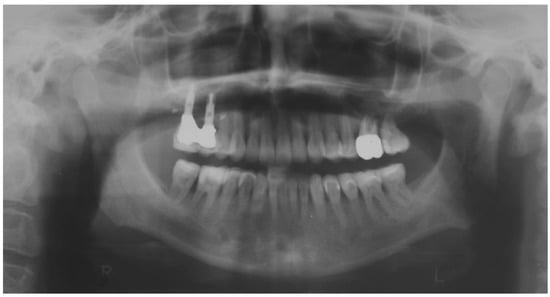

2.2. Clinical Example

2.3. Outcome Achieved